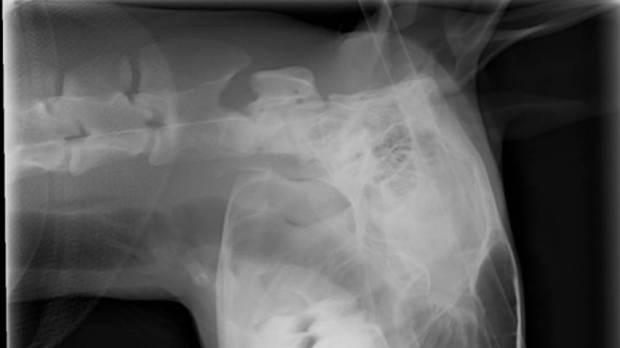

中箭袋鼠的X光图片